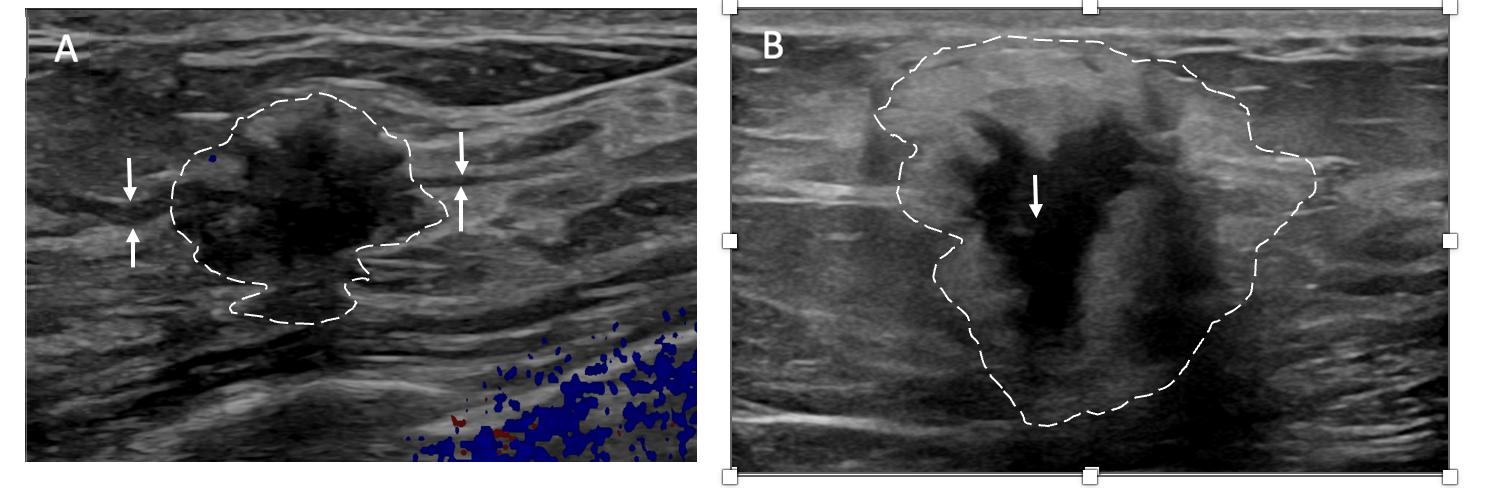

Ultrasound of the breast. Office-based cryoablation is optimized for treatment of ultrasound-visible breast cancers. Consequently, breast ultrasound should be performed of all suspicious imaging abnormalities to assess eligibility for ultrasound-guided cryoablation.

Ultrasound permits assessment of the cancer’s proximity to the overlying skin and underlying chest wall and also enables detection of changes in adjacent tissue architecture (e.g., edema, tissue distortion, extension of tumor into adjacent ducts) and could indicate the presence of more extensive disease that would need to be incorporated into the treatment plan (Image 2).

Proximity (< 5 mm) of a cancer to the skin is generally regarded as a contraindication to cryoablation, but a safe skin distance can sometimes be created using hydrodissection

Image 2. Image A shows dark, dominant, irregular mass encircled by hash marks with intraductal tumor extensions (dark bands bracketed by paired arrows) extending from left and right sides of dominant mass. Image B shows dark, irregular dominant mass (arrow) surrounded by peri-tumoral edema outlined by hash marks